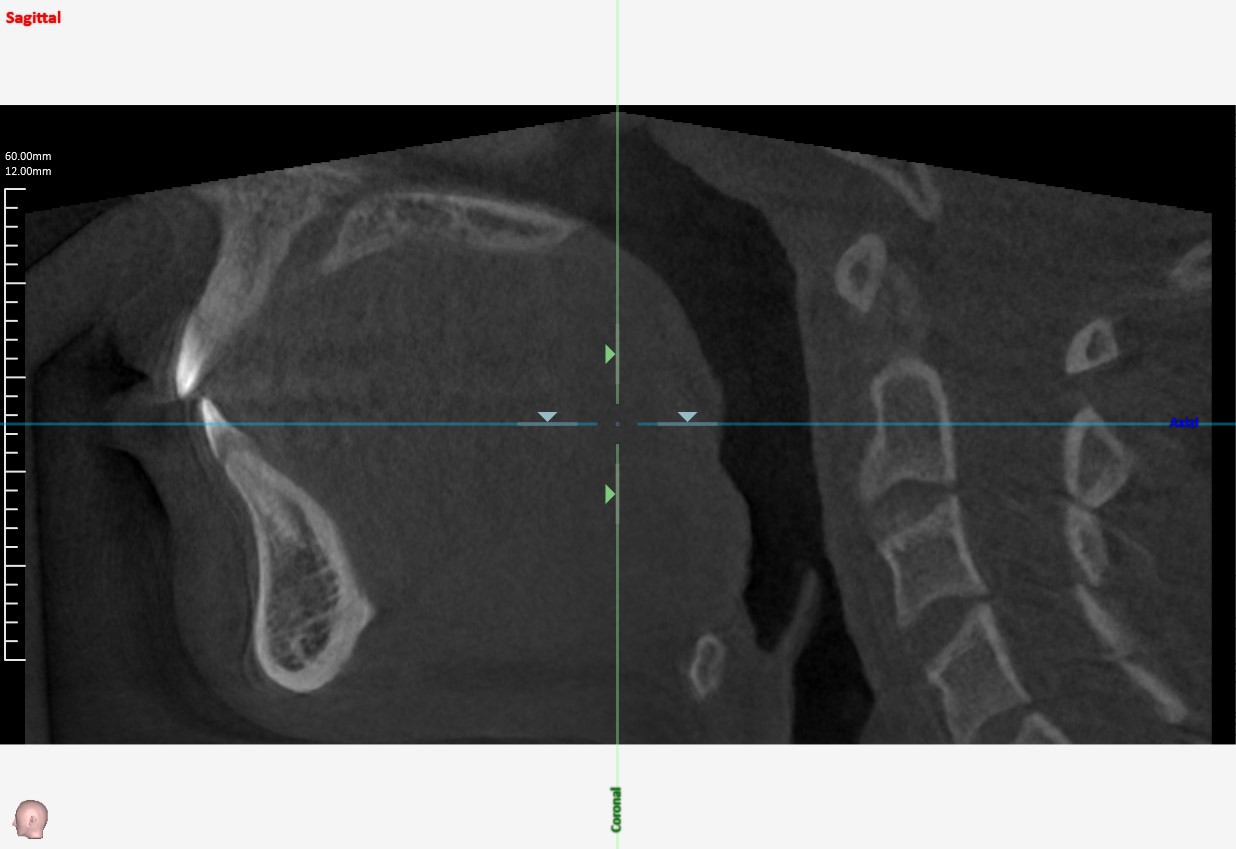

咽頭CT